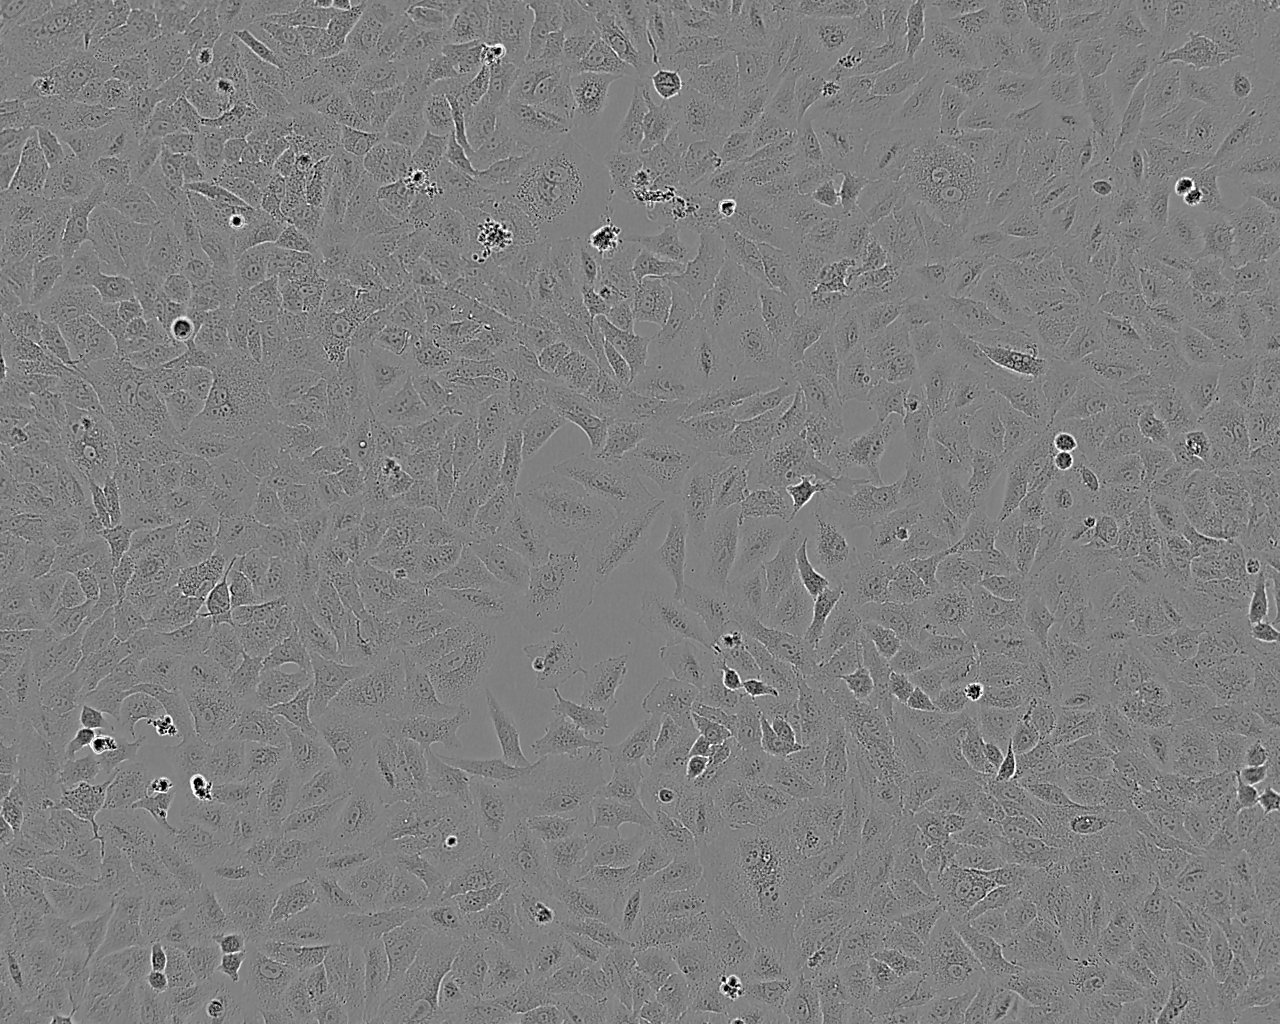

细胞背景资料:该细胞来源于人胰腺癌裸鼠异种移植产生的癌性腹水,可以表达CEA,人胰腺相关抗原、人胰腺特异性抗原和黏蛋白。

细胞形态:上皮细胞样

细胞生长:贴壁

细胞生长特性:贴壁生长